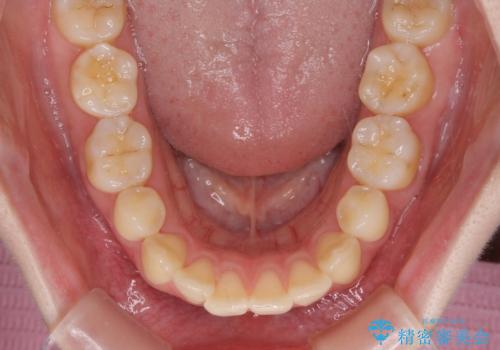

舌の突出癖が原因で後戻りをしたため、舌のトレーニングをしっかりと行っていただき、口元の突出感を改善することができました。

インビザラインの装着時間が守れず、1年強で終わる予定でしたが、4年間を要することとなりました。

- マウスピース型矯正装置の長時間装着(1日20時間以上)が必須です

- 治療計画通りに進めるためには、患者様の意志が重要になります